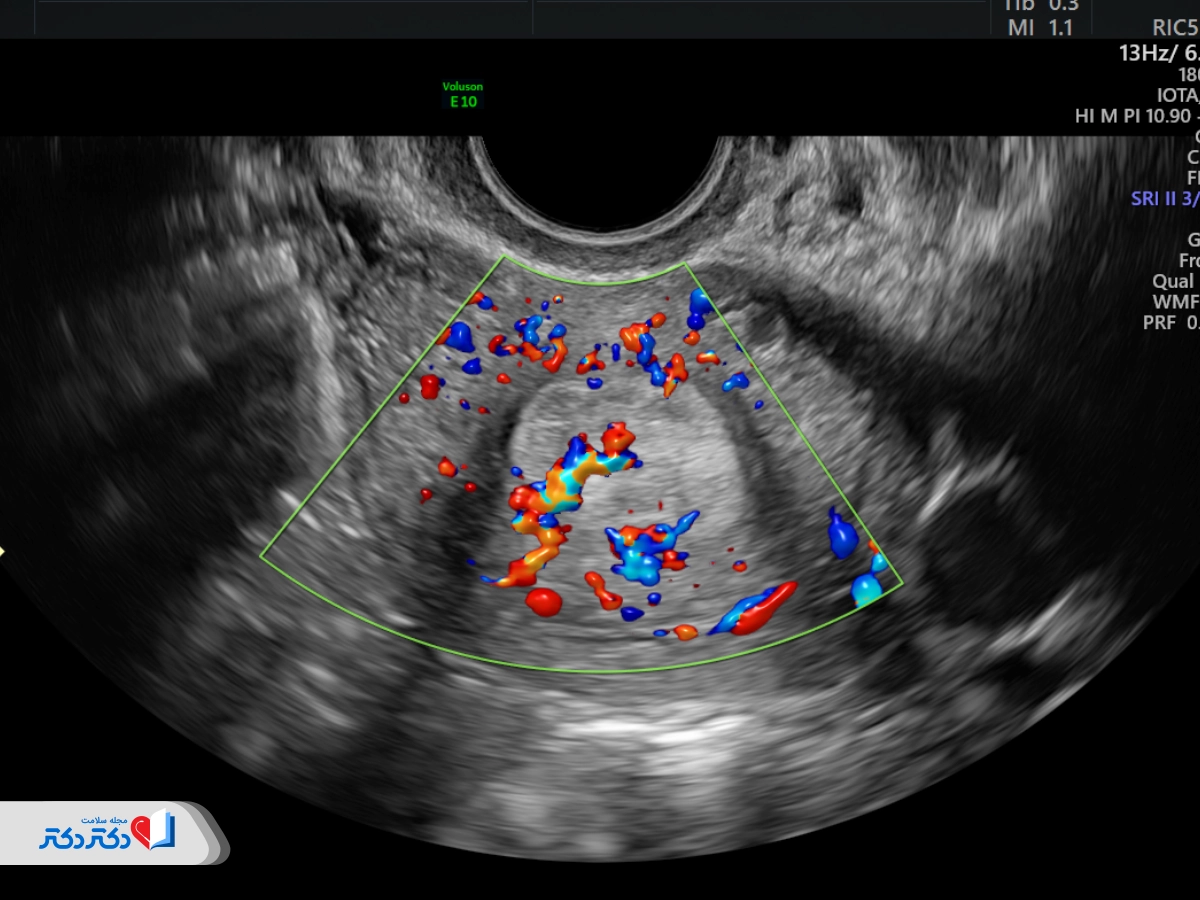

سونوگرافی داپلر رنگی

سونوگرافی داپلر رنگی که به آن سونوگرافی کالر داپلر هم میگویند، شامل یک رایانه است که امواج صوتی را به رنگهای مختلف تغییر میدهد تا جهت جریان خون مشخص شود. نوع و شدت رنگها سرعت و جهت جریان خون را نشان میدهد.

نوع جدیدتری از داپلر رنگی است که برای نشاندادن وجود جریان خون استفاده میشود. داپلر قدرتی حتی رگهای خونی بسیار کوچکتر و جریان خون کندتر را نشان میدهد؛ چیزی که کالر داپلر از پس آن برنمیآید. بااینحال، داپلر قدرتی جهت جریان خون را ثبت نمیکند. پزشکان معمولا از داپلر قدرتی فقط برای مطالعه جریان خون در داخل اندامها استفاده میکنند نه جهت آن.